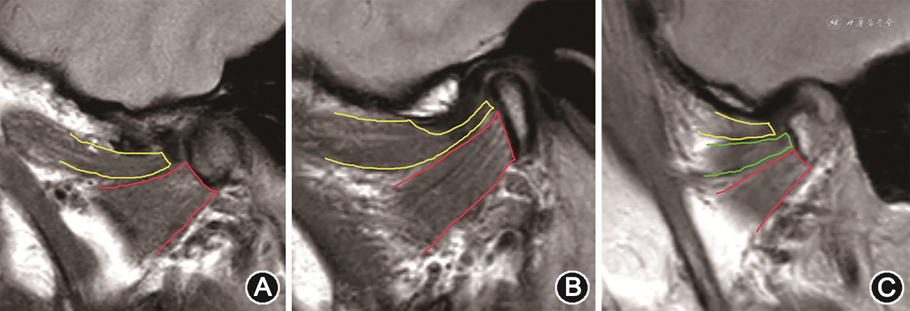

翼外肌通常分为上头和下头。上头主要作用于下颌闭口、后退和同侧运动,下头是在开口、前伸和对侧运动中起作用[5, 6]。上头起自蝶骨大翼颞下面,止于关节盘、部分关节囊、翼状窝及髁突;下头起自翼突外板外侧面,止于翼状窝及髁突颈部[7]。上头附着点通常分为3种类型:Ⅰ型,上头附着于关节盘,下头附着于髁突;Ⅱ型,上头附着于关节盘和髁突,下头附着于髁突;Ⅲ型,上头附着于关节盘,翼外肌的中间部分(上、下头汇合处发出)及下头附着于翼状窝及髁突(图1)[4,6, 7]。多数研究发现翼外肌上头附着点与关节盘移位的差异并无统计学意义[5, 6,8, 9, 10]。

注:黄线示翼外肌上头;红线示翼外肌下头;绿线示翼外肌中间部分